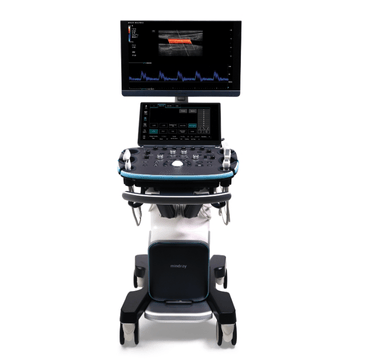

Ultrasound Machines

As the healthcare industry faces pressure to improve patient outcomes and reduce costs, clinicians are turning to ultrasound for a more cost-effective, real-time, and patient-friendly imaging alternative. Mindray North America offers innovative, leading-edge, accessible ultrasound machines that empower you to provide the highest quality of care now and in the future. Experience peace of mind and see something better with Mindray Ultrasound.

Mindray Ultrasound Machines

Ultrasound is a game-changing solution as the healthcare industry faces pressure to improve patient outcomes and reduce costs. MindrayŌĆÖs cutting-edge ultrasound machines offer a more cost-effective, real-time, and patient-friendly imaging alternative, with innovative technologies that can help improve patient outcomes and reduce costs. Explore our range of ultrasound machines, tailored to meet the needs of various medical departments.